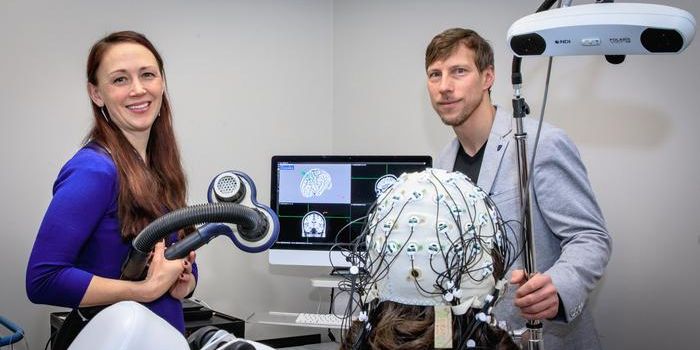

FEB 02, 2025Clinical & Molecular DXScientists have created a new kind of test for autism, which relies on motion tracking technology that tracks as a parti ...